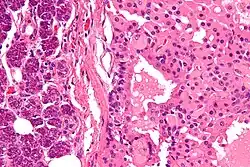

Onkocytoma – guz zbudowany z komórek nabłonkowych lub mioepitelialnych zwanych onkocytami[1].

Onkocyty są to komórki nabłonkowe lub mioepitelialne o ziarnistej eozynochłonnej (kwasochłonnej) cytoplazmie. Komórki te charakteryzują się obecnością dużej liczby mitochondriów w cytoplazmie bez ziarnistości mitochondrialnych. Wykazują dużą aktywność enzymów oksydacyjnych. Prawidłowo występują pojedynczo lub w niewielkich grupach nabłonka gruczołów ślinowych, tarczycy (komórki Hürthla), przysadki, przytarczyc (komórki oksyfilne), nerek, trzustki, nadnerczy, jajowodu i wątroby[1].